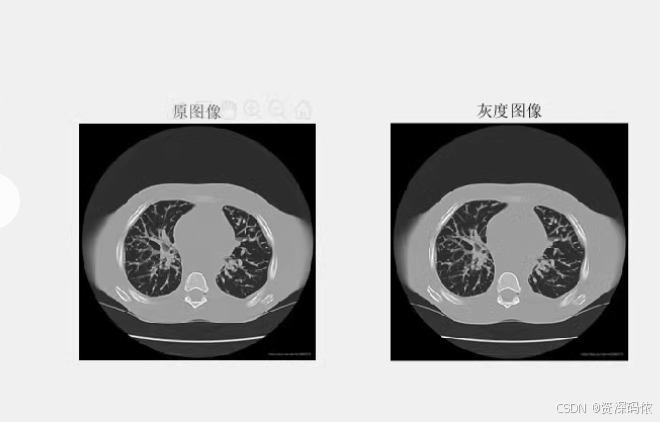

% 读取并显示原始图像

originalImg = imread('your_image_file.jpg'); % 替换为你的图像文件名

imshow(originalImg);

title('Original Image');

% 将图像转换为灰度图像

grayImg = rgb2gray(originalImg);

% 显示灰度图像

figure;

imshow(grayImg);

title('Grayscale Image');